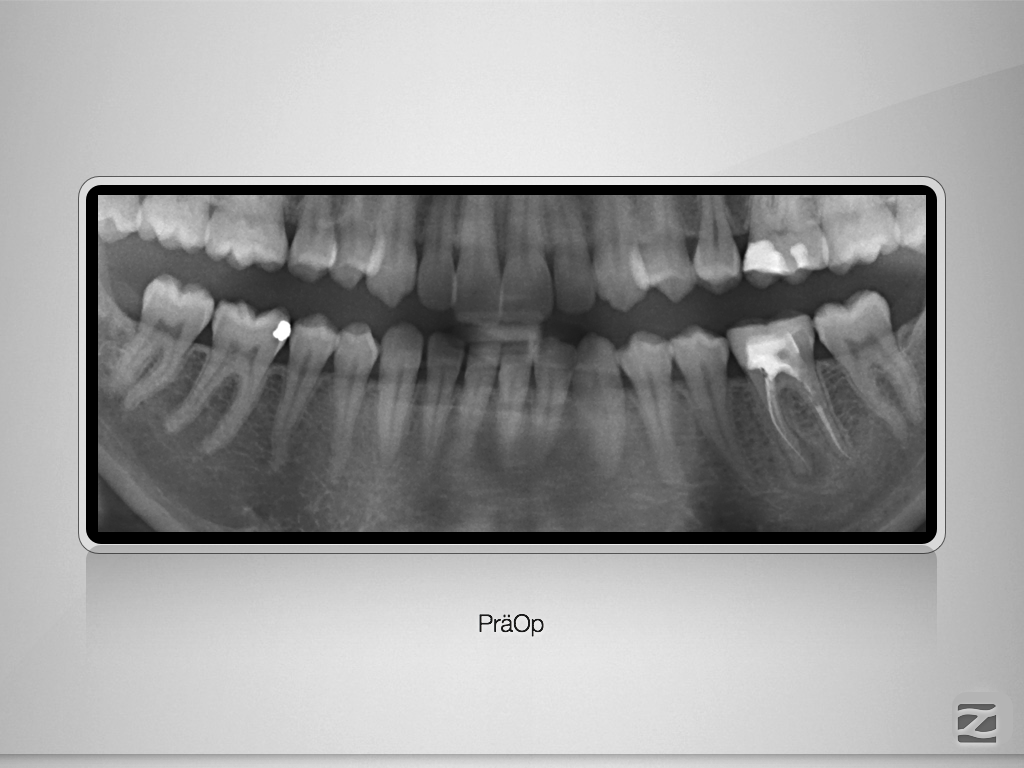

Fraktur auf voller Arbeitslänge